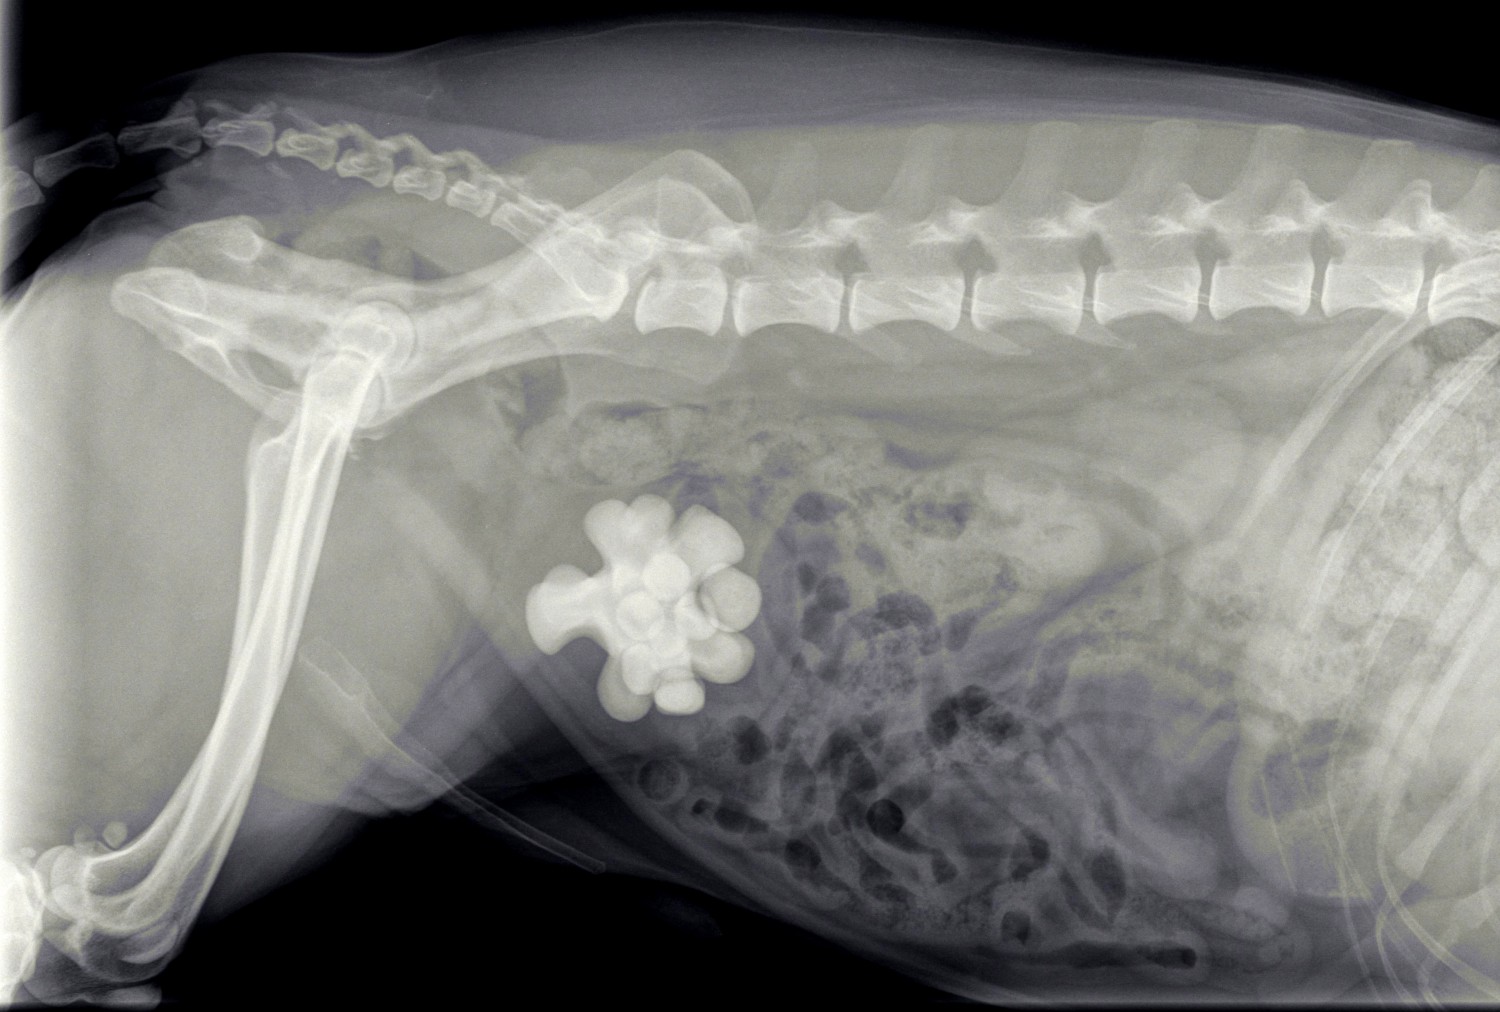

Spike is een zwarte kruising reu uit Rijswijk die in augustus bij de dierenarts op consult kwam vanwege het laten lopen van urine. De urine stonk ook behoorlijk en Spike lekte overal. Bij het urine-onderzoek viel onder andere op dat er zeer veel ontstekingscellen in de urine aanwezig waren, maar geen gruis. Bij het klinisch onderzoek voelde we in de omgeving van de blaas een structuur, die daar niet hoorde te zitten. In overleg met de eigenaar zijn we overgegaan tot het maken van röntgenfoto’s.

Spike had last van blaasstenen, terwijl we daar in het urine-onderzoek geen aanwijzingen voor hadden gevonden. Omdat Spike al bijna 10 jaar oud was hebben we met een bloedonderzoek eerst zijn nieren en lever getest. Vervolgens hebben we Spike geopereerd om de stenen te verwijderen.

De grote verassing kwam met het feit dat het niet om een verzameling van kleine steentjes ging, zoals meestal. In dit geval ging het om één hele grote steen en meerdere kleinere.